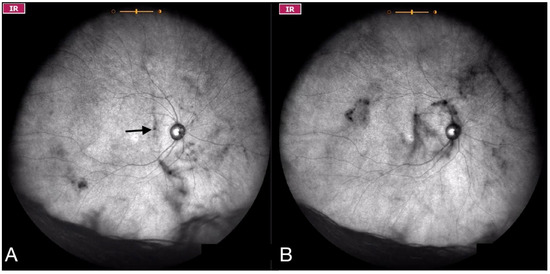

Figure 6.

Ultra-widefield IRcSLO images of an eye with Grade 4 vitreous floaters. (A) Several diffuse shadows are observed when the eye is in primary gaze. A dense shadow is observed in the macular area (arrow). (B) Vitreous opacities are stirred after a saccadic movement and denser shadows are observed inside the macular area. See also Video S6.